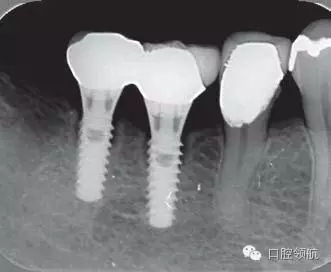

修復(fù)體安裝后的2003年1月復(fù)診時(shí)的X線片上,沒有發(fā)現(xiàn)種植體頸部有骨吸收現(xiàn)象,情況良好(圖2)。但是,2003年8月,因混合陶瓷樹脂部分修復(fù)體的破損而進(jìn)行再制作時(shí),發(fā)現(xiàn)有輕度的咬合疼痛以及舌側(cè)頸部的牙齦有輕壓痛??趦?nèi)沒有觀察到該部位的牙齦紅腫。X線片可以觀察到(左下第6顆牙) 的種植體頸部有達(dá)到第4螺紋的骨吸收現(xiàn)象(圖3)。

圖3(左下第6顆牙)的種植體的骨吸收達(dá)到第4螺紋(2003年8月)